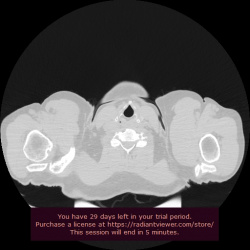

Муж. 34 лет, упал с высоты 4 м. Резкие боли в левом подреберье, вынужденной положение сидя согнувшись. При УЗИ брюшной полости - признаков повреждения нет. На Рентгенограмме грудной клетки...